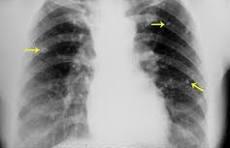

De acordo com a Fundação Oswaldo Cruz (Fiocruz), a tuberculose é uma doença transmitida por uma bactéria (bacilo) chamada Mycobacterium tuberculosis. Embora afete principalmente os pulmões, ela também pode atingir outros órgãos e sistemas do nosso corpo, sendo transmitida pelo ar, quando as pessoas infectadas tossem, espirram ou cospem.

Os sintomas mais comuns da doença envolvem tosse com ou sem secreção (catarro) por mais de quatro semanas; cansaço; febre baixa, geralmente à tarde; suor noturno; falta de apetite; palidez; perda de peso; e fraqueza; Muitas vezes, porém, esses sintomas são levas e duram por meses, o que acarreta numa demora na busca por atendimento médico. Contudo, é fundamental buscar auxílio o quanto antes, para que o tratamento funcione e também para evitar infectar outras pessoas.